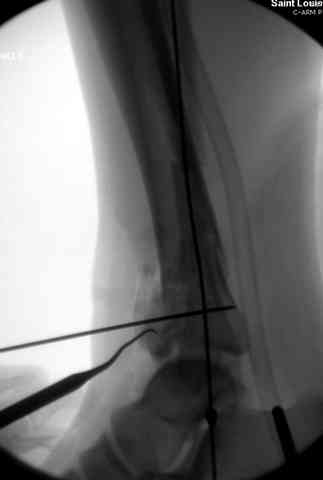

При лечении внутрисуставных переломов типа "Pilon"

или "Tibial Plateau" на голени, применение простых

наружных фиксаторов типа "Spanning ExFix" или "Travelling ExFix" стал одним из стандартом этапного лечения.

В первые часы после поступления больным экстренно накладывается простой фиксатор из двух поперечно проведенных стержней или сооружается "Delta

Frame" в зависимости от места локализации, и проводится дистракция.

Дополнительные ренгенограммы после дистракции и

обязательная комьютерная томография дают возможности разузнать топографию расположения фрагментов, что немаловажно для планирования хирургического доступа.

По апексу фрагмента ориентируется при планировании

фиксации, также предоперационно определяется

направление фиксирующего материала: шурупа или спицы с упорной площадкой.

Здесь выставлена пара случаев перелома пилона, оба

случая леченные этапным наружным фиксатором.